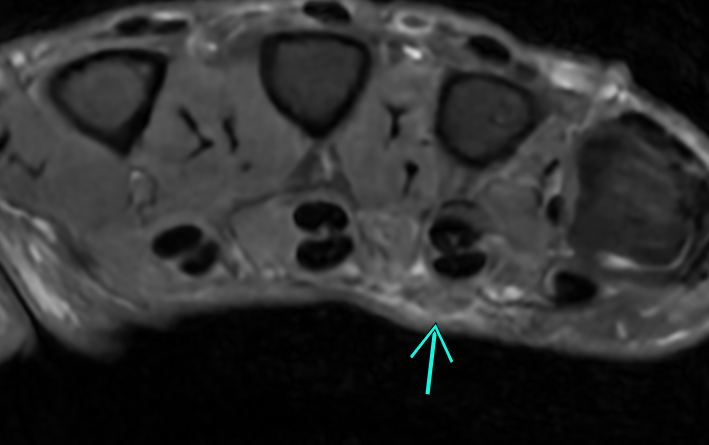

Duyputren's disease on MRI

here an example of early duyputrens disease on MRI with pretendinous cords. Can be hard to see. here a great article with amazing illustrations! https://radsource.us/dupuytrens-disease/ have you seen this before on MRI?

https://www.cmrad.com/cases/2034814042 companion case